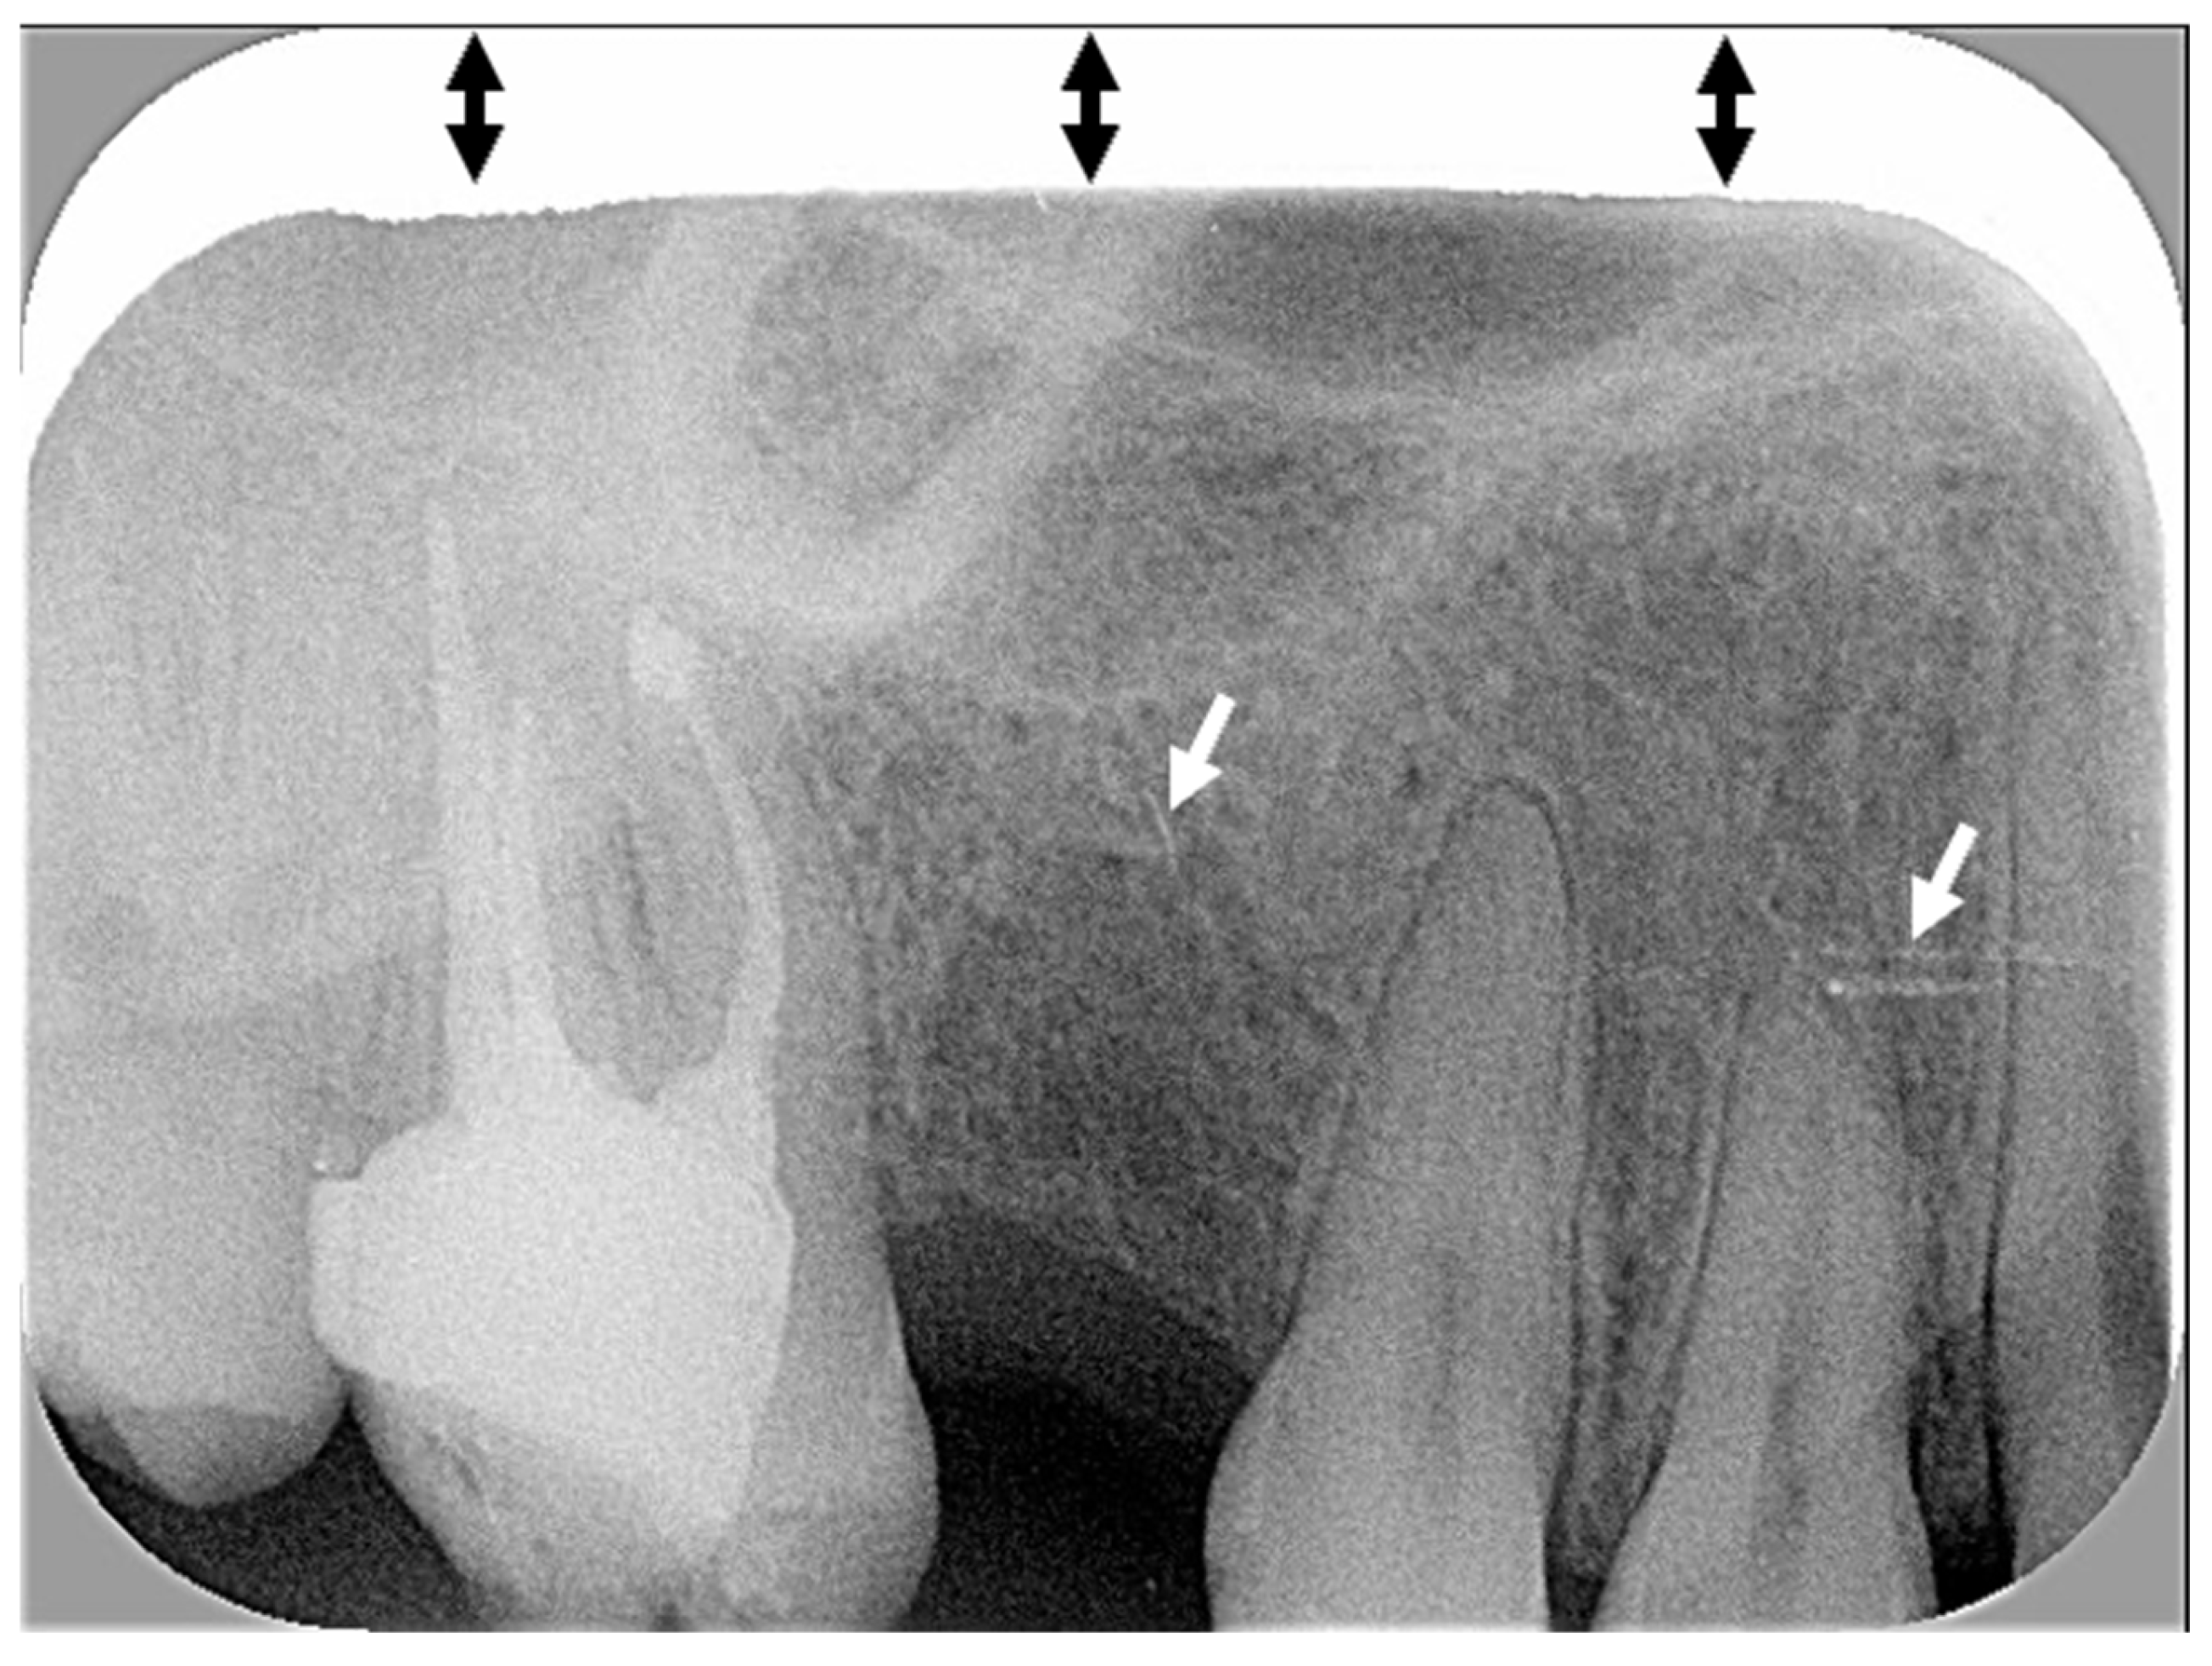

| Cone centering (with or without rectangular collimator) | Image outline Tooth fully visible | Complete image outline; borders not cut No truncated image | Incomplete image outline; image cut without consequences on diagnosis | Incomplete image outline; image cut with consequences on diagnosis |

| Centering of the digital plate | Target tooth: >2 mm of periapical bone is visible AND visible periapex of adjacent anterior tooth (size 1) or two adjacent teeth (size 2) | -- | Yes | No (one of the two parameters is not fulfilled) |

| Mesial and distal view of front tooth (size 1), or of two adjacent teeth (size 2) | -- | Yes | No | |

| Tooth fully visible (from crown to apex) | -- | Yes | No | |

| Correct bite on the film-holder | -- | Yes | No | |

| Axis of the digital plate | Correct axis of plate | -- | Yes | No |

| No vertical distortion | No distortion (absence of tooth shortening or lengthening) | -- | Yes | No |

| Image contrast | Correct image contrast | -- | Yes | No (too bright or too dark) |

| Artefacts | Exposure to ambient light, presence of foreign object or vertical stripes | -- | No Or minimal without consequence on diagnosis | Yes With consequence on diagnosis |

| Intact digital plate, without traces of scratches, folds, or other | -- | No Or minimal without consequence on diagnosis | Yes With consequence on diagnosis | |

| Overall X-ray quality | Overall quality | Excellent overall quality | Acceptable quality; minor errors | Major error; interpretation is difficult |